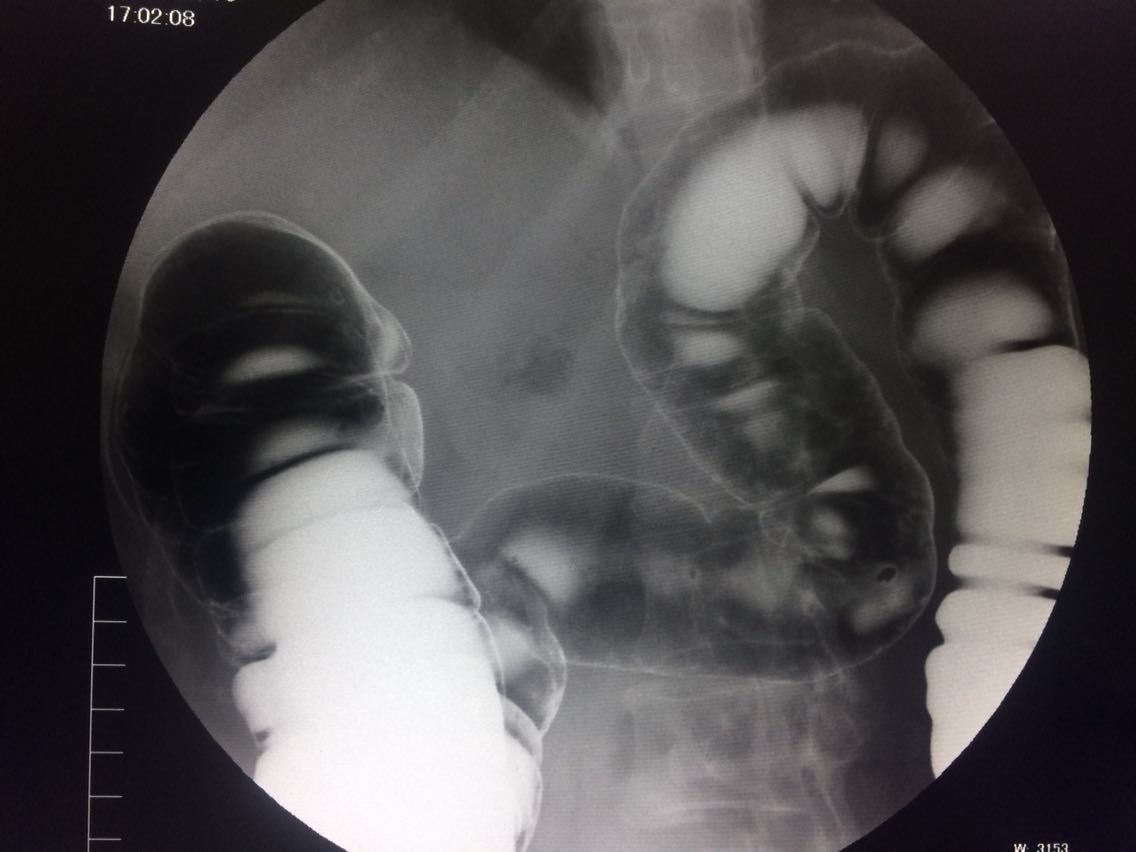

间断右下腹疼痛6年余。 6年来,无诱因出现右下腹痛,间断发生,呈胀痛,可忍受,压痛,无反跳痛。 既往:3年前,做肠镜未见明显异常。

查体,右下腹压痛。 入院做钡灌肠造影。

考虑升结肠占位。 完善术前各项检查。手术治疗。